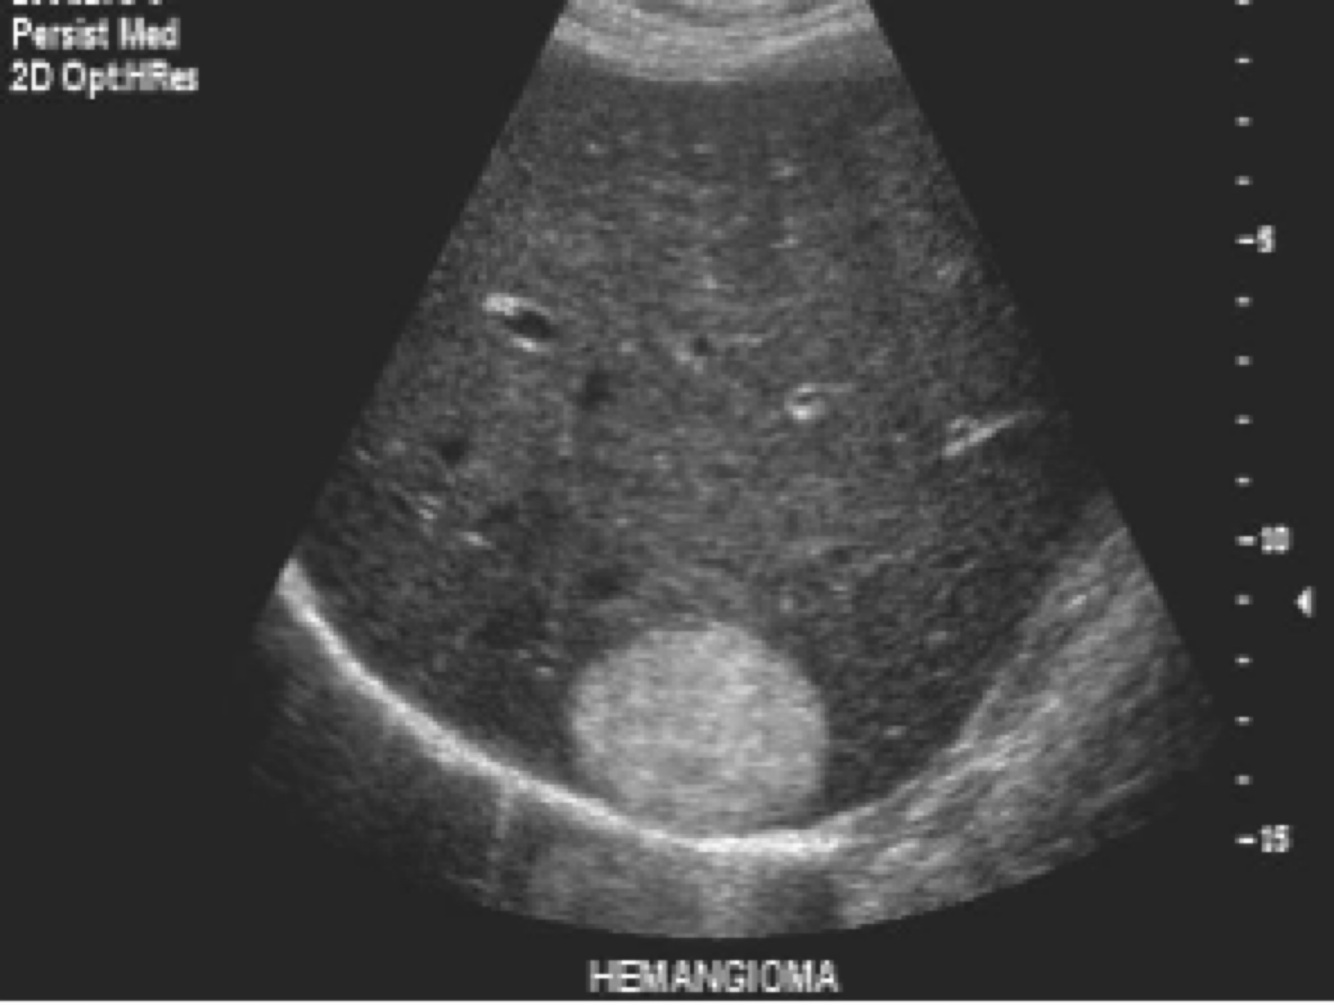

What kind of mass is this?

Hyperechoic